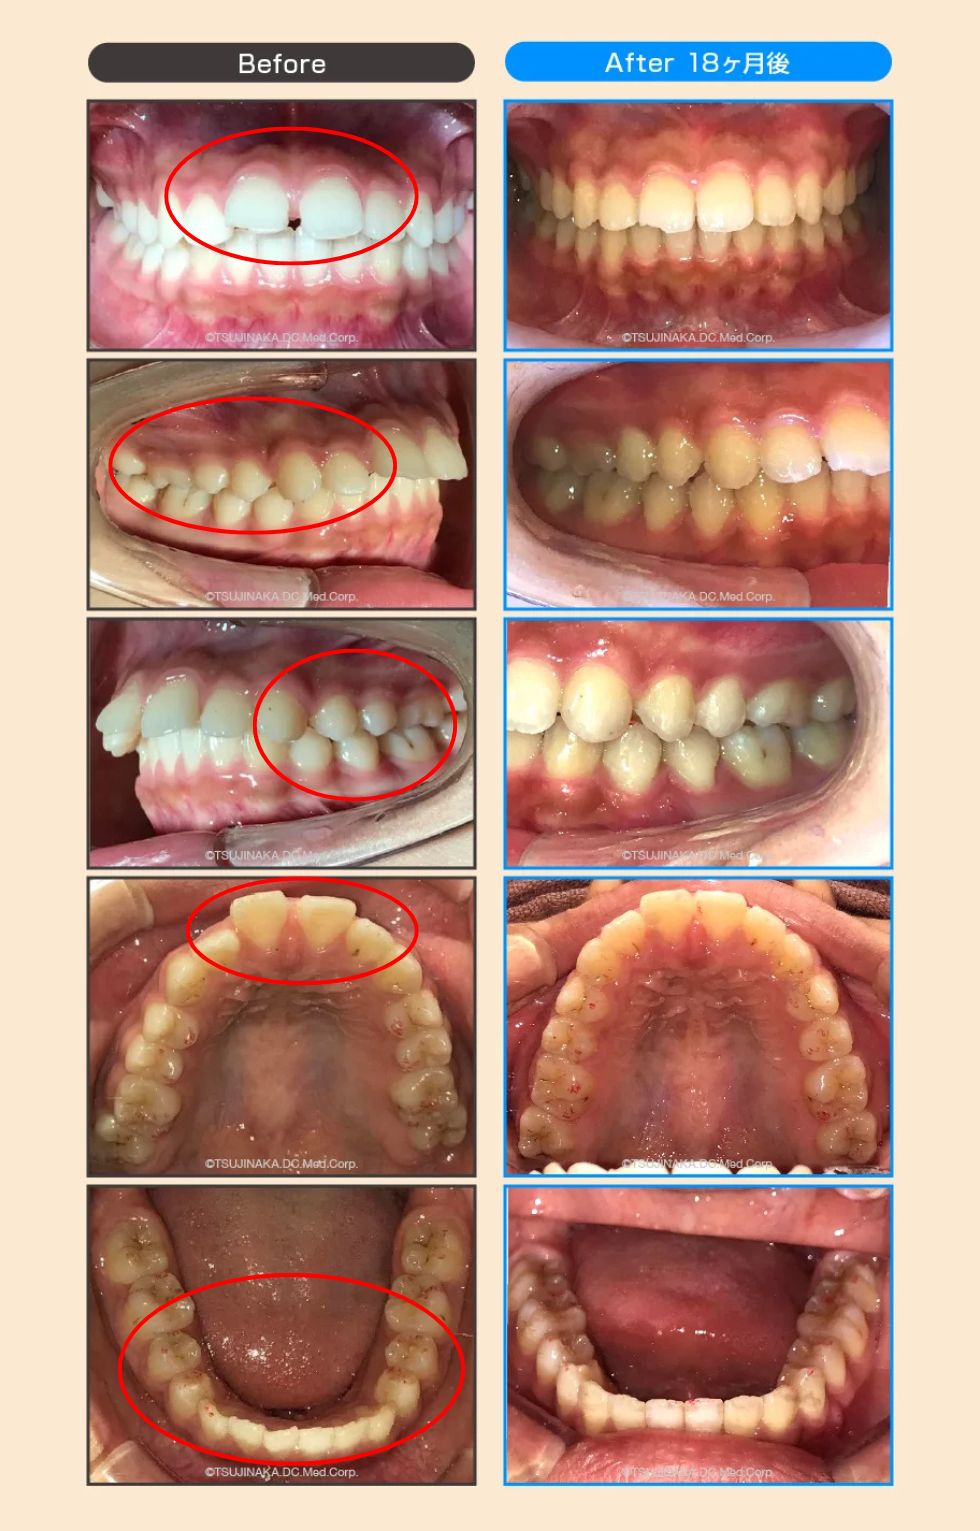

【症例No.7345】小学校の頃から歯が前に出ているのとすきっ歯が気になっていた

小学校の頃から歯が前に出ているのとすきっ歯が気になっていた

前歯のすき間や前歯が出ていることが気になるとのことでご相談いただきました。マウスピース型矯正装置を用いた矯正治療を行い、必要に応じて顎間ゴム(ゴム掛け)を併用しながら、歯列・咬合関係の改善を目指しました。

| 主訴 | 前歯のすき間(すきっ歯)と前歯が出ていることが気になる |

| 診断名 | 歯間離開(正中離開)/上顎前突/下顎叢生 |

| 治療期間 | 2年(※個人差あり) |